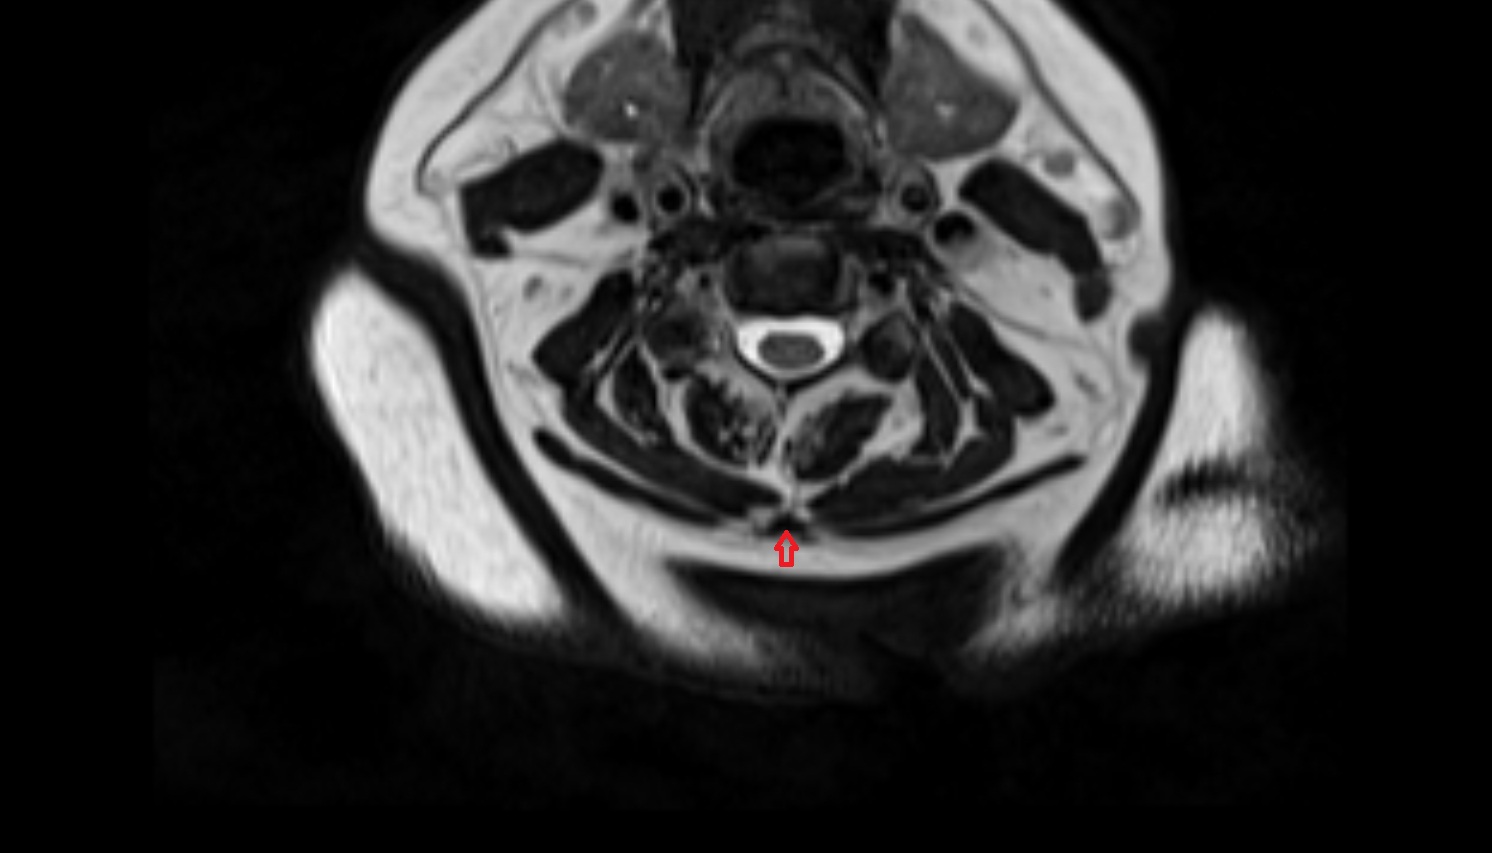

- Median aperture of fourth ventricle (foramen of Magendie)